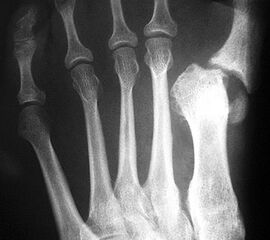

Pseudarthrose

Eine verzögerte Knochenheilung wird bei distalen Osteotomien in Zusammenhang mit einer gestörten Durchblutung des Metatarsale I gesehen 26. Für proximale Osteotomien wird die Pseudarthroserate mit ca. 3 % angegeben 27 (Abbildung 20). Möglicherweise bietet das minimalinvasive Vorgehen bezüglich der Knochenheilung Vorteile 28. Läßt sich anhand konventioneller Röntgenaufnahmen der Verdacht nicht bestätigen, kann mit einem CT eine fehlende Überbauung meist zweifelsfrei belegt werden.

Neuere Studien unterstreichen die Rolle von Vitamin D3 bei der Knochenheilung. Brinker et al. (2007)29 fanden in über 80% der Patienten mit verzögerter Knochenheilung endokrinologische Auffälligkeiten, die sich durch eine medikamentöse Substitution behandeln ließen. Dies gilt insbesondere für einen erniedrigten Vitamin D3 Spiegel im Serum. Die optimistische Einschätzung des Effektes einer Ultraschallbehandlung bei verzögerter Knochenheilung und Pseudarthrosebildung konnten wir anhand eigener Daten bisher nicht reproduzieren 3031. Aktuelle Arbeiten sehen die Rolle der Ultraschallbehandlung vor allem als adjuvantes Verfahren nach operativer Revision einer Pseudarthrose 32. Bei gelockertem Osteosynthesematerial, Korrekturverlust und/oder Verkürzung des Metatarsale ist die Indikation zur operativen Revision gegeben. Die Pseudarthrose wird ausgeräumt und die Defektzone mit Spongiosa aufgefüllt (Abbildung 21). Aufgrund der höheren osteogenen Potenz bevorzugen wir bei der Pseudarthrosenrevision Spongiosa vom Beckenkamm 33.